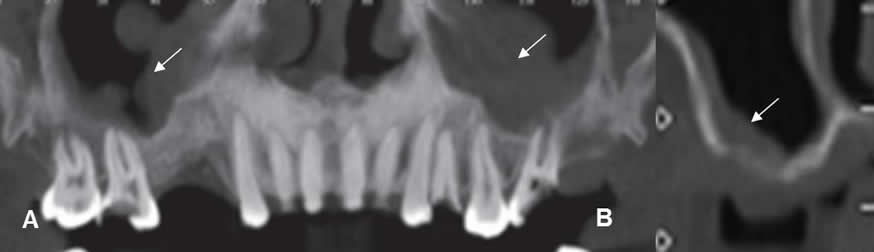

Fig 28. Atrofia ósea.

A: Ortopantografía y B: Panorámica de dentascan. Ausencia de piezas, con atrofia de la cresta alveolar maxilar y mandibular en A y del maxilar en B.